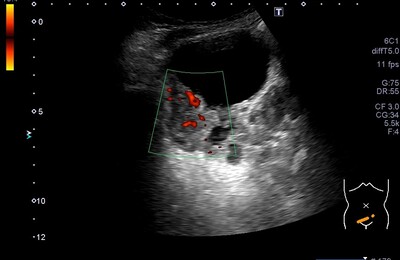

1年以上のお久しぶりです(//∇//)。こんにちは。 2026年になっちゃいました💦寒いので こたつの中で記事を書きたいですが、こたつが無い。。。 今回は肉眼的血尿で受診の、膀胱のエコー画像になります。 静止画です⇩ 膀胱右側壁に隆起性病変を認めます。 膀胱 CTでも膀胱右側壁に腫瘍が確認でき、膀胱鏡検査へ。 CS:膀胱右側壁、右尿管口外側から頂部右側まで続く約3㎝ほどの乳頭状広基性腫瘍。と記載さ…